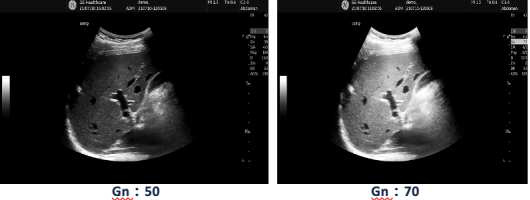

8 O, `% E2 F% p! B" p* i9 O2 O& D 总增益和时间增益补偿(Gain/TGC) & Y. Z. r% h* Q! B, q

增益控制是用来使整个视野中,不同患者组织和相似的声学特性具有一致性,总增益可在整个扇窗内同时调整图像亮度。为显示血液中少数弱回声和心内膜血液组织界面,增益应被设置到足够高。 . w1 x! f+ y& H) i. Y

时间增益补偿(Time gain compensate, TGC)控制为一系列可调单元,用来弥补由于超声信号深入人体内部时,其强度和振幅的缺失。因此,扇区近场的回声振幅较远场强。有选择性的放大信号强度可使结构的外观在整个扇区中一致。 1 K! O" _# {1 E+ l/ b# ?